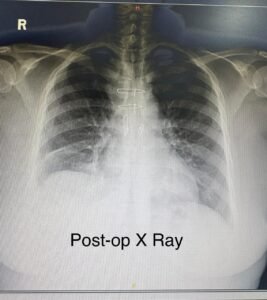

ಎದೆಗೂಡಿನಿಂದ (ಸುಪೀರಿಯರ್ ಮೀಡಿಯಾಸ್ಟಿನಂನಿಂದ) ಕುತ್ತಿಗೆಗೆ ಹರಡಿರುವುದರಿಂದ ಈ ಸಿಸ್ಟನ್ನು ಎದೆಗೂಡಿನ ಮುಖಾಂತರ ಆಪರೇಷನ್ ಮಾಡುವ ಸಮಯದಲ್ಲಿ, ಈ ಸಿಸ್ಟ್ ಇನ್ನೊಮಿನೇಟ್ ಆರ್ಟರಿ (Innominate Artery) ಮತ್ತು ಇನ್ನೊಮಿನೇಟ್ ವೇಯ್ನ್ ಗಳಿಗೆ (Innominate Vein) ಅಂಟಿಕೊಂಡಿದ್ದು , ಟ್ರೇಕಿಯವನ್ನು (Trachea – ದೇಹದ ದೊಡ್ಡ ಹಾಗೂ ಮುಖ್ಯವಾದ ಶ್ವಾಸನಾಳ) ಎಡಕ್ಕೆ ತಳ್ಳಿದ್ದು ಕಂಡು ಬಂದಿದೆ. ಆದರೂ ಯಾವುದೇ ಸಮಸ್ಯೆ ಇಲ್ಲದೇ ಎಚ್ಚರಿಕೆಯಿಂದ ಸಿಸ್ಟ್ ಅನ್ನು ಸ್ವಲ್ಪನೂ ಬ್ರೇಕ್ ಮಾಡದೇ ಜೋಪಾನವಾಗಿ ಹೊರತೆಗೆಯುವಲ್ಲಿ ಡಾ. ರಾಘವೇಂದ್ರ ಚಿಕ್ಕಾತೂರ್ ಯಶಸ್ವಿಯಾಗಿದ್ದಾರೆ.

ಅಪರೇಷನ್ ನಡೆದು ಒಂದು ವಾರಕ್ಕೆ, ಯಾವುದೇ ಸಮಸ್ಯೆ ಇಲ್ಲದೇ ಎಂದಿನಂತೆ ತಮ್ಮ ದೈನಂದಿನ ಜೀವನ ನಡೆಸಲು ಅನುಕೂಲವಾಗಿದೆ. ಇಂತಹ ಸಮಸ್ಯೆಗಳಿಗೆ ಸರಿಯಾದ ರೇಡಿಯೋಲಾಜಿಕಲ್ ಪರೀಕ್ಷೆ ಹಾಗೂ ಶಸ್ತ್ರ ಚಿಕಿತ್ಸೆ ಮೂಲಕ ರೋಗಿಗೆ ಇರೋ ನಿಜವಾದ ಸಮಸ್ಯೆಯನ್ನುತಿಳಿದು ಬಳಿಕ ಅದಕ್ಕೆ ಸೂಕ್ತ ಪರಿಹಾರ ಹುಡುಕಲು ಅನುಕೂಲವಾಗುತ್ತದೆ ಎಂದು ಮೆಡಿಕವರ್ ಆಸ್ಪತ್ರೆಯ ಕಾರ್ಡಿಯೋಥೋರಾಸಿಕ್ ಸರ್ಜನ್ ಡಾ. ರಾಘವೇಂದ್ರ ಚಿಕ್ಕಾತೂರ್ ಅಭಿಪ್ರಾಯ ಪಟ್ಟಿದ್ದಾರೆ .